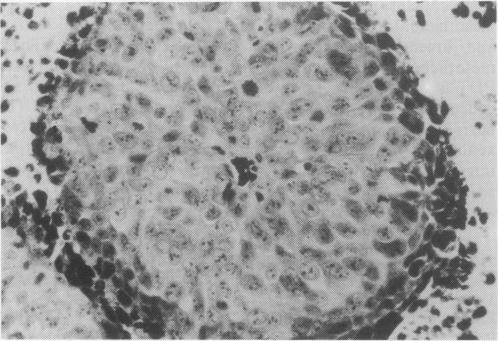

We have examined the effectiveness of photodynamic therapy against R3230AC rat mammary adenocarcinoma and human mesothelioma as xenografts in the same host. The results demonstrate that the xenografted human tumour is significantly more responsive to photodynamic treatment than the rodent mammary tumour. Studies also showed that the mesothelioma xenograft was fluence rate- and fluence-dependent while the rat tumour exposed to the same conditions demonstrated neither of these dependencies. This disparity in response was not attributable to a difference in either whole-tumour uptake or subcellular distribution of the porphyrin photosensitiser. Analysis of the effects of visible irradiation on cytochrome c oxidase activity, measured in mitochondria prepared from tumours borne on hosts injected with photosensitiser, demonstrated that photoradiation-induced enzyme inhibition was significantly greater in mesothelioma than in R3230AC mammary tumour preparations. However, in parallel studies conducted in vitro, when photosensitiser and light were delivered to previously unperturbed mitochondria, rates of enzyme inhibition were not significantly different. Both tumours were established in long-term cell culture. While the uptake of porphyrin photosensitiser was equivalent in both cell lines, the R3230AC cells displayed a significantly greater photosensitivity than the mesothelioma cells. The data presented here demonstrate that the mechanisms that govern response to photodynamic therapy are complex, but in the case of these two xenografted tumours host response to therapy is not likely to play a significant role.

我们已经研究了光动力疗法对R3230AC大鼠乳腺腺癌和人恶性间皮瘤作为同一宿主中的异种移植物的有效性。结果表明,异种移植的人类肿瘤对光动力治疗的反应明显比啮齿动物乳腺肿瘤更敏感。研究还表明,间皮瘤异种移植物对光通量率和光通量有依赖性,而暴露于相同条件下的大鼠肿瘤则没有这些依赖性。这种反应差异并非归因于卟啉光敏剂在全肿瘤摄取或亚细胞分布上的差异。对在注射了光敏剂的宿主身上产生的肿瘤所制备的线粒体中测量的可见辐射对细胞色素c氧化酶活性的影响进行分析表明,光辐射诱导的酶抑制在间皮瘤中比在R3230AC乳腺肿瘤制剂中显著更大。然而,在体外进行的平行研究中,当光敏剂和光作用于先前未受干扰的线粒体时,酶抑制率没有显著差异。两种肿瘤均建立于长期细胞培养中。虽然两种细胞系中卟啉光敏剂的摄取相当,但R3230AC细胞显示出比间皮瘤细胞显著更高的光敏性。此处呈现的数据表明,控制对光动力疗法反应的机制很复杂,但就这两种异种移植肿瘤而言,宿主对治疗的反应不太可能起重要作用。